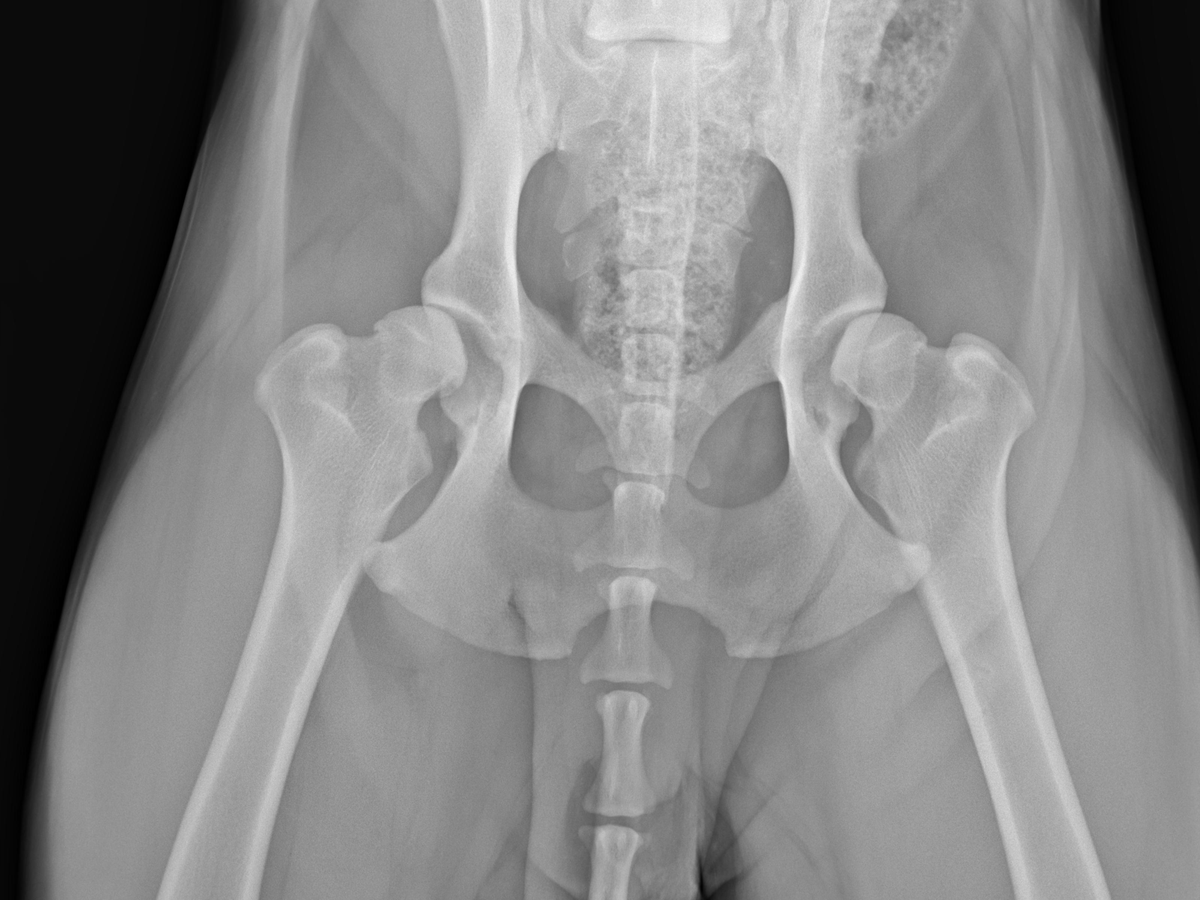

In November 2021, we rescued our dog Zimba, a Dogo Argentino, from a neglectful household that only kept him in a cage. At that time, he was 11 months old. As he spent more time with us, we noticed some unusual changes in his way of walking. His back legs would slip under him more and more often, and it would take less and less time for him to catch a break while going on walks. When we took him to the vet, he was diagnosed with severe hip dysplasia and arthritis in his hind knees.

Right now, he's being treated with injections and supplements to slow down the progression and to reduce some pain. To recover his full mobility, the vets recommend immediate surgery to fully replace his hip and knee joints. These procedures are too expensive for us at the moment. We humbly ask anyone to please donate any amount to help us cover the expenses of his treatment.

The surgery has an estimated price of up to $3800, and extra funds will be needed to cover post-operation procedures.